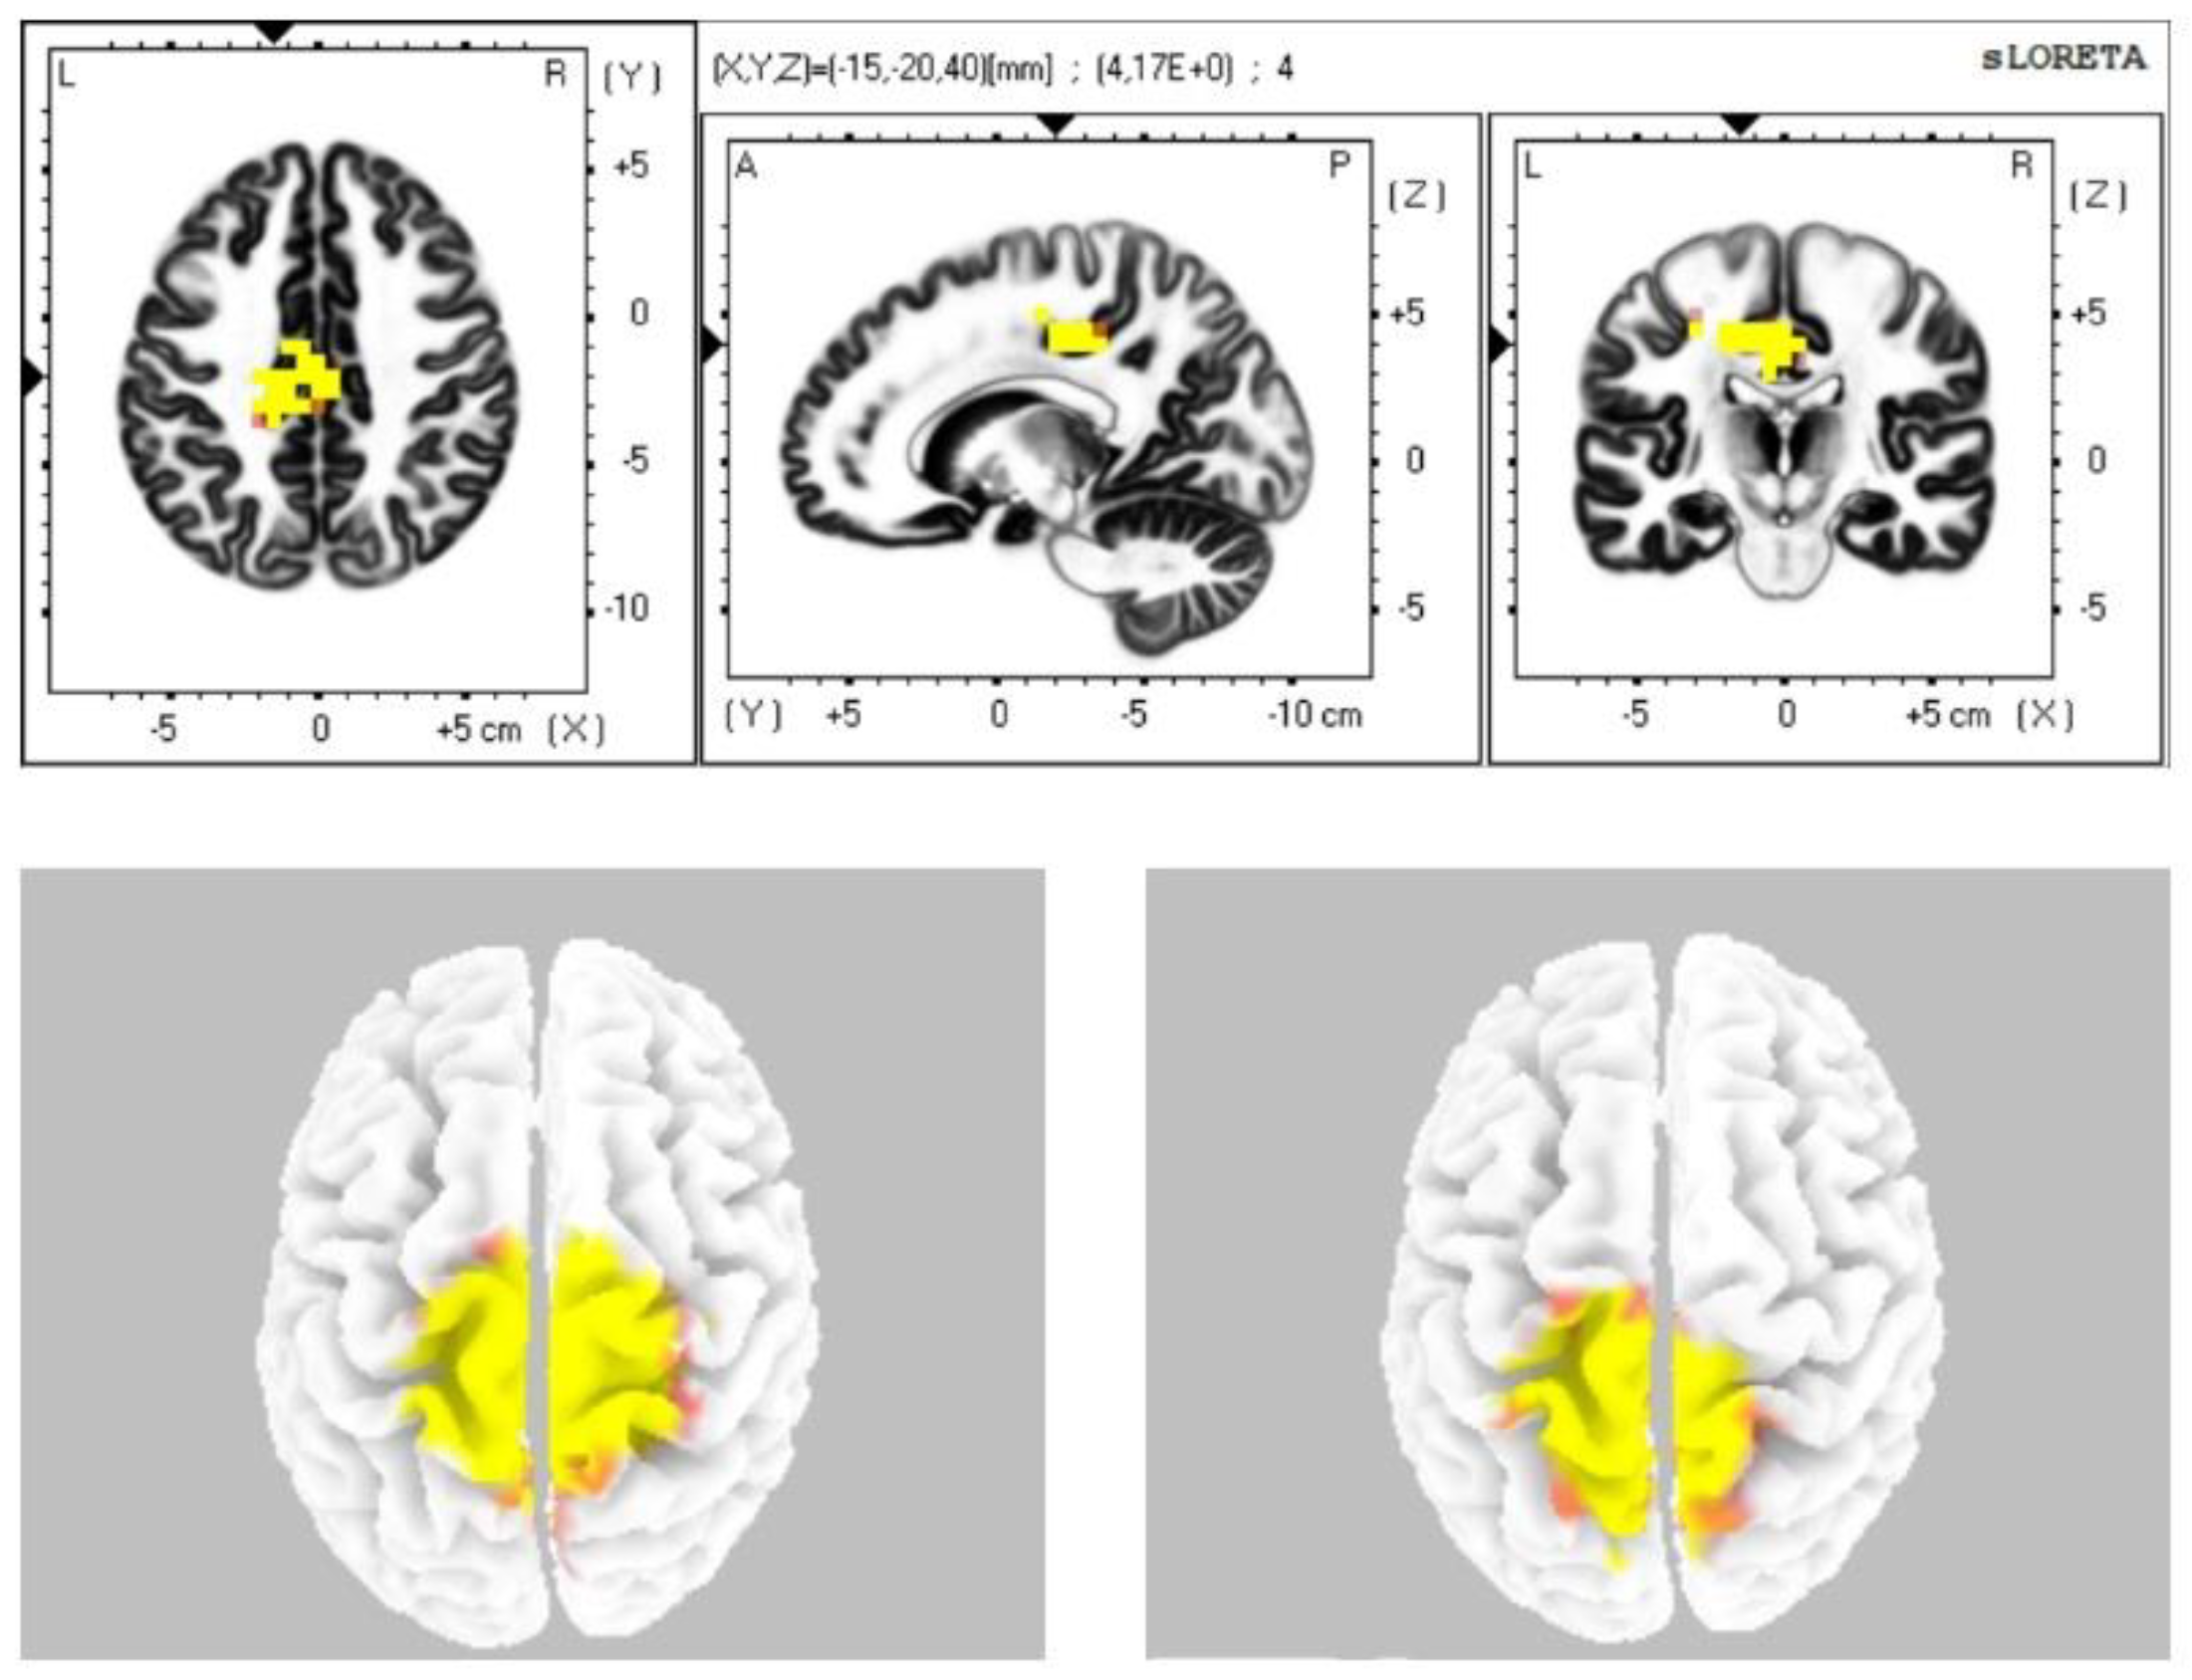

| Alpha-2 | 24, 31, 23, 6 |

| Beta-1 | 6, 7, 31 |

| Beta-2 | 6, 7 |